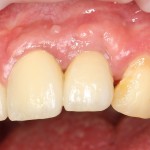

Около трёх лет назад к нам в клинику обратилась пациентка Мария, на момент обращения ей было 45 лет. Её беспокоила ситуация с передними резцами:

В ходе беседы она рассказала, что лечит эти зубы всю сознательную жизнь — их депульпировали («удалили нерв») из-за последствий травмы еще в школьном возрасте, и после этого каждые несколько лет (а то и чаще) ей приходилось перелечивать каналы, менять коронки, вкладки и т. д.

В результате, зубы приобрели очень уж нездоровый вид (см. фото выше). Вдобавок, всё усугубилось существенным снижением качества жизни — коронки и вкладки из зубов постоянно выпадают, десна вокруг них кровоточит при чистке…. Кроме того, Марию не покидает ощущение того, что эти зубы могут просто вывалиться в самый неподходящий момент. Именно это заставило её обратиться в нашу клинику.